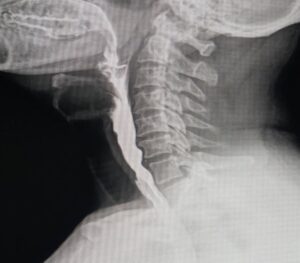

Exame utilizado para analisar tórax, crânio, seios da face, abdômen simples e contrastados e sistema músculo esquelético.

O Raio X Contrastado usa o mesmo equipamento digital, mas acrescenta uma substância contrastante ao paciente.

Realizado com Raio X, o exame possibilita flagrar aspiração traqueal, atrasos ou compensações musculares em menos de um segundo.